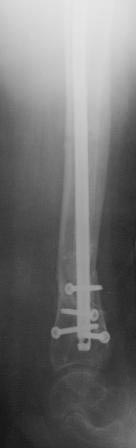

Результат БИОСа ложного сустава большеберцовой кости |

Уважаемые коллеги , 30.04.15 года был представлен случай ложный сустав б/берцовой кости, с БИОС. (http://weborto.net/forum/1430415118/),

тогда коллеги просили показать исход операции. прошла чуть больше двух месяцев, пациентка ходит самостоятельно с одной тростью, вес большой более 100кг., функция г/стоп почти восстановлен, ось голени правильный( жаль забыл фотографировать).